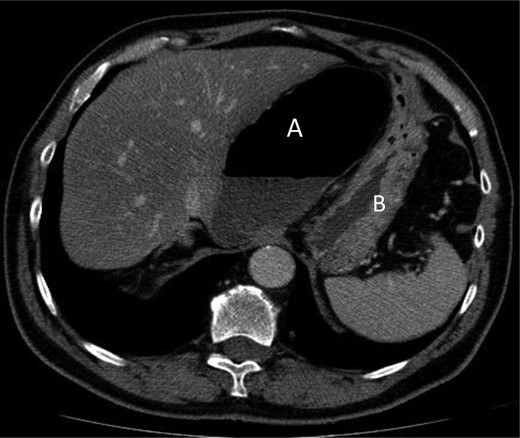

A 69-year-old patient presented to our emergency room with progressive dull abdominal pain and distension without nausea, vomiting or change in bowel habits. Physical examination showed pain with moderate guarding in the right upper and lower quadrants. A plain abdominal X-ray and a CT scan were performed. Radiological findings suggested the diagnosis of an internal hernia through the epiploic foramen and containing the right colon with important distension of the caecum (Fig. 1). Surgical exploration was then performed using an open approach. At laparotomy, we found an internal herniation of the caecum and the entire ascending colon through the foramen of Winslow (Figs 2 and 3). After hernia reduction, multiple patchy areas of caecal necrosis were observed (Fig. 4). A formal right hemi-colectomy was therefore performed. The postoperative recovery was uneventful.

Coronal slice showing herniation of right colon through the foramen of Winslow.